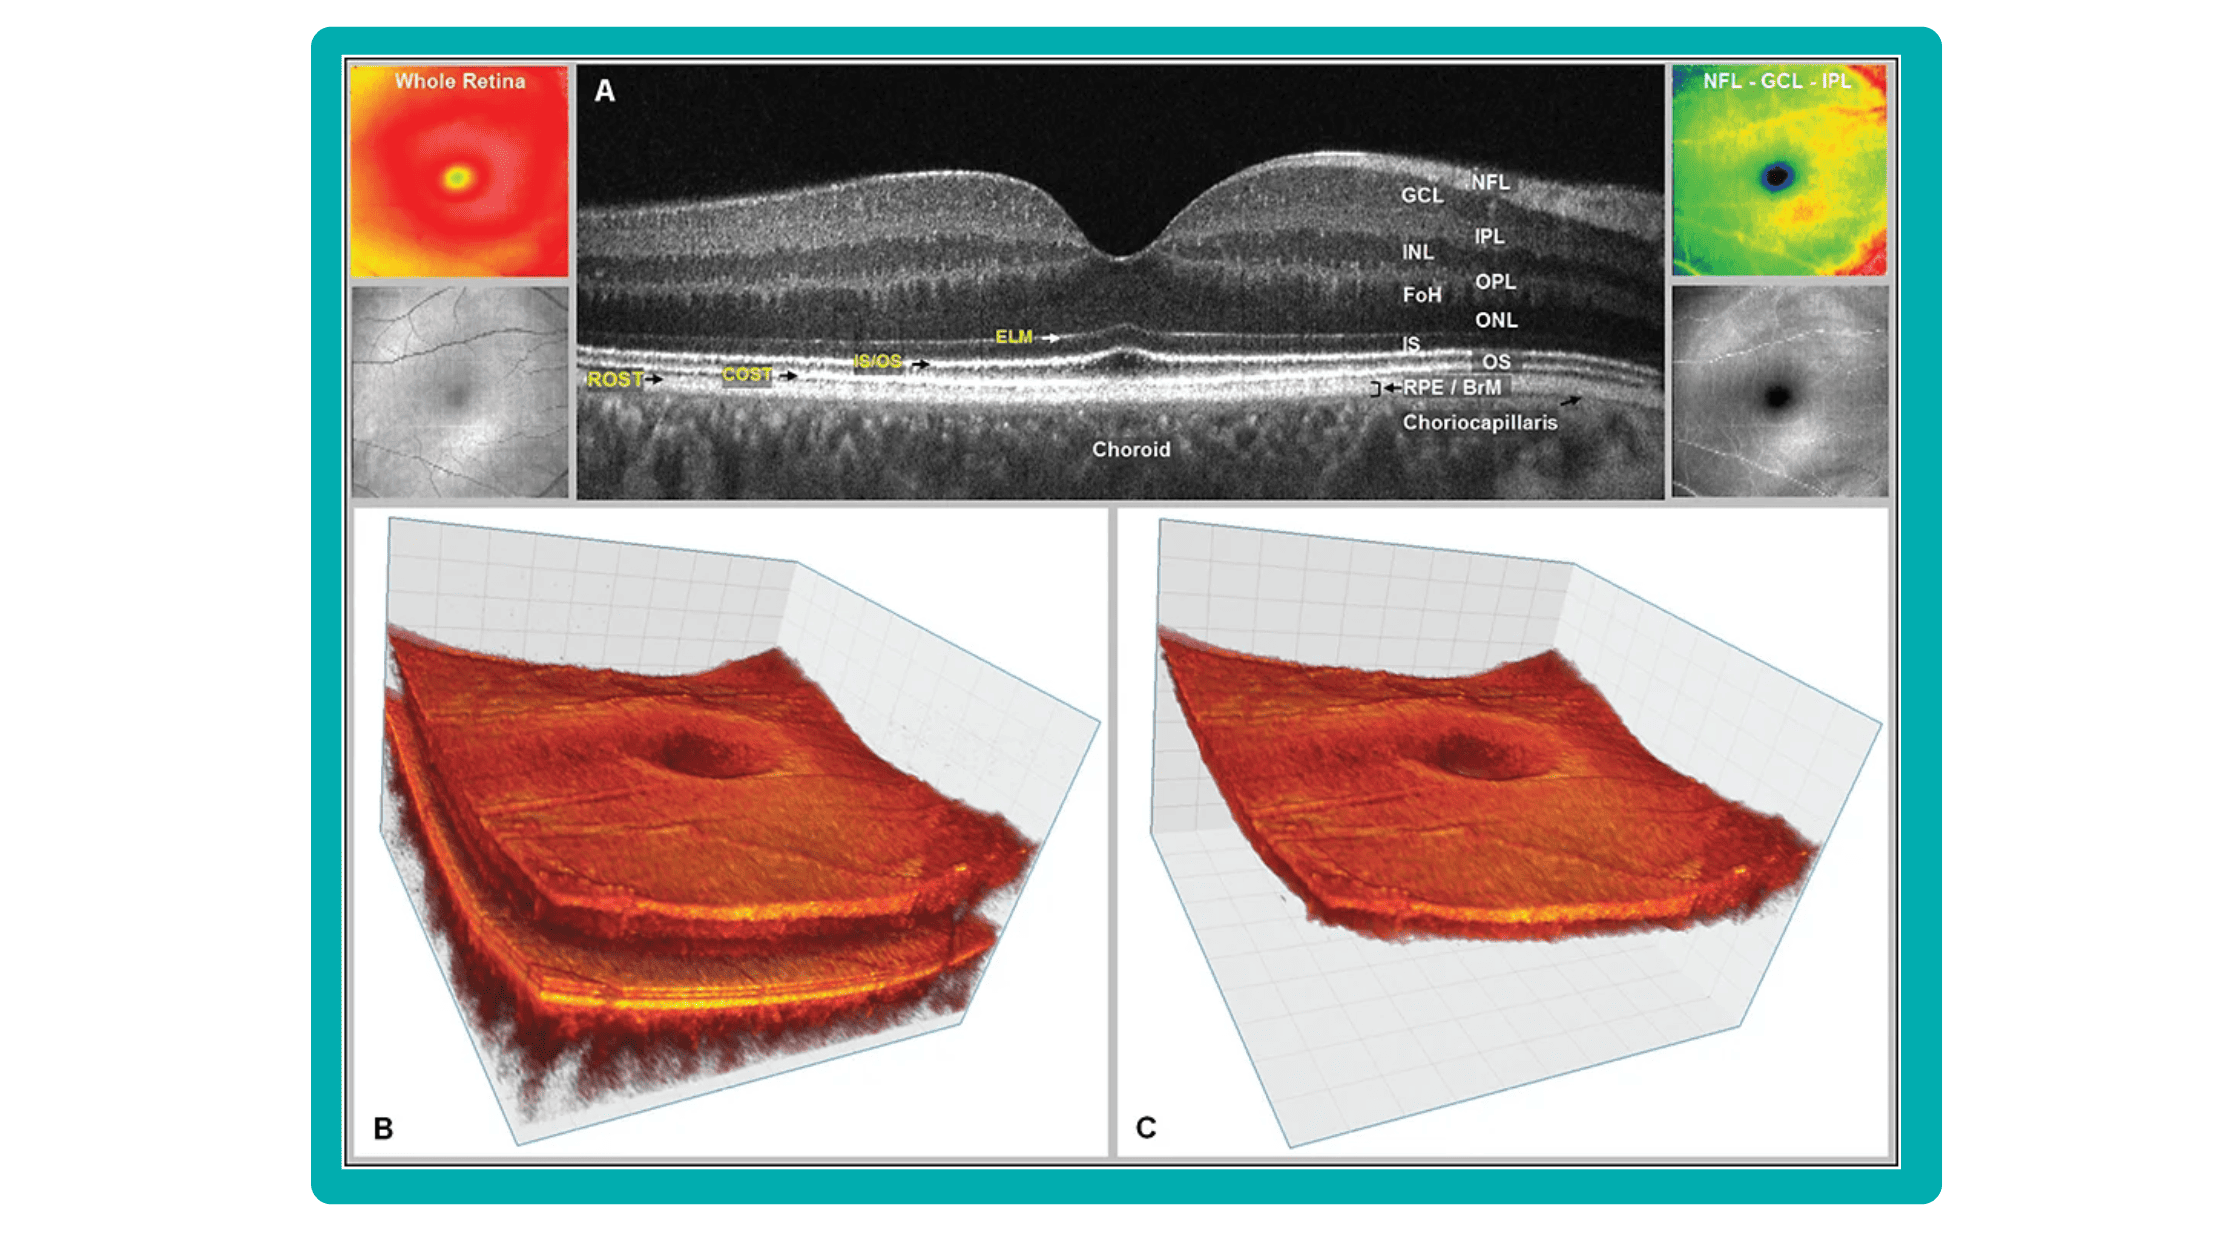

New Tech in Optometry: New Iterations of OCT

Even though OCTs entered the market relatively recently, they swiftly became indispensable ancillary tests in ophthalmic practice for many professionals. The primary reason is their high-quality imaging of the retina, nerve fiber layer, and optic nerve, offering a near in-vivo “optical biopsy” of the retina.

New Tech in Optometry: En-face OCT

En-face OCT in current systems is based on software reconstruction of OCT images. Image slices are selected retrospectively from full recorded volumes or calculated by depth projection along specific depth ranges, enabling three-dimensional data visualization in a fundus projection. This technique allows the projection of specific retinal and/or choroidal layers at a given depth onto an en-face view.

While we are more accustomed to working with cross-sectional images (B-scans), microstructural changes and the retinal and choroidal vasculature morphology are challenging to evaluate using B-scans alone. En-face OCT offers numerous advantages, including the ability to precisely localize lesions within specific subretinal layers using their axial location on OCT cross-sections and to register projected OCT images to other fundus imaging modalities using retinal vessels as landmarks.

Currently, en-face OCT is being applied to various specialized areas within the eye, encompassing the anterior segment, glaucoma, infectious diseases, and the retina.

Optometry Technology: SS-OCT

Like SD-OCT, swept-source OCT (SS-OCT) utilizes Fourier domain technology to optimize higher-quality wavelength transduction within the frequency domain. This enables rapid sweeping scan patterns across a broad bandwidth.

However, instead of a broad-bandwidth light source projected all at once, as in SD-OCT, SS-OCT employs a single tunable laser that sweeps through different frequencies to cover the entire spectrum swiftly. The light reflected from the eye is captured by a photodetector significantly faster than the charge-coupled device (CCD) camera used in SD-OCTs. This difference translates to a faster scanning speed of up to 400,000 axial scans per second, eliminating the typical depth-dependent signal drop-off associated with SD-OCT. Additionally, the faster scanning speed reduces image distortions caused by eye movements and allows for wider B-scans, facilitating widefield imaging.

Furthermore, many SS-OCT systems utilize a light source centered at an approximately 1050 nm wavelength, providing better tissue penetration than SD-OCT. This allows for visualization of structures like the choroid, lamina cribrosa, and structures at the anterior chamber angle. This enhanced penetration is crucial in diseases like Central Serous Chorioretinopathy, where evaluating the entire thickness of the choroid can be challenging.

Moreover, volumetric analysis of the choroid and various pathological features can aid in monitoring the progression of Wet AMD, CSCR, and Diabetic Retinopathy, as well as assessing the response to treatments such as anti-VEGF agents, laser photocoagulation, and photodynamic therapy (PDT).

OCT has become a golden standard for diagnosing and monitoring many ocular pathologies, thanks to its unparalleled level of detail in ophthalmic imaging.

While retinal reports vary among OCT models, they typically include:- a foveally centered B-scan,

- a quantitative thickness map,

- and a semi-quantitative thickness map.

The B-scan offers a visual snapshot of foveal architecture and confirms proper scan centering. The quantitative thickness map employs the ETDRS sector map to measure retinal thickness within a 6mm circle around the fovea, with specific measurements for the foveal sector (1mm), inner macular ring (3mm), and outer macular ring (6mm).

Progression analytics enable comparison of serial macular scans, which is invaluable for managing vitreomacular interface disorders and macular edema. The semi-quantitative thickness map provides a broader overview of retinal thickness throughout the scan.

Given this amount of data, it is challenging to identify subtle and localized retinal pathological changes. As a result, entire OCT datasets are represented by few aggregated values, and the standard OCT reports generated by most devices often rely on significant data reduction to simplify interpretation, which you can usually not customize.

OCT report interpretation: 3 methods exist for displaying OCT data

Firstly, acquired 2D image slices are presented individually. This allows for detailed examination, but navigating through numerous images can be cumbersome, particularly with large datasets.

Secondly, a fundus image is displayed with superimposed retinal layers. This facilitates linking layers to the fundus, but only one layer can be examined at a time, hindering the analysis of multiple layers simultaneously.

Thirdly, the OCT tomogram is visualized in 3D, providing a comprehensive overview, but adjusting the visual representation often has limitations. Additionally, combined 3D visualizations of the tomogram and layers are typically unavailable, potentially obscuring spatial relationships.